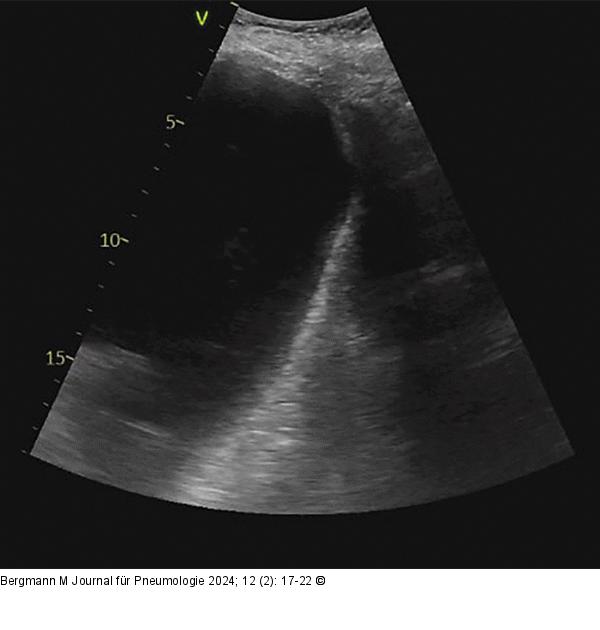

Abbildung 7: Abgeplattetes/invertiertes Zwerchfell

Abgeplattetes/invertiertes Zwerchfell im Ultraschall |